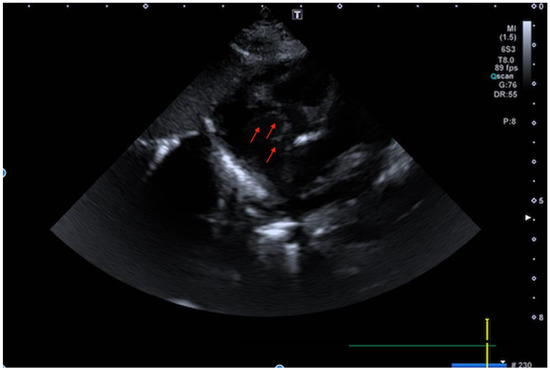

Chest X-ray was unremarkable except for the incidental finding of a right clavicular fracture. The baby therefore underwent a full cardiac investigation. Electrocardiogram was unremarkable. Trans-thoracic echocardiogram (TTE) showed situs solitus, levocardia with normal systemic and pulmonary venous returns, along with atrio-ventricular and ventriculo-arterial concordance. Although showing all correct components and a normally opening pulmonary valve, the right-sided chambers appeared somewhat small for a newborn still in a transitional stage. In the right atrium (RA), there was a membrane arising from the inferior vena cava (IVC), much like a Eustachian valve, but it appeared both to reach the interatrial septum and, being very mobile, to intermittently engage through the tricuspid valve orifice (Figure 1, and Supplementary Materials Videoclip S1–S3). Tricuspid antegrade flow was clearly demonstrated, and therefore the membranous structure was initially interpreted as a redundant Eustachian valve and the hypoxia attributed to postnatal maladjustment.

Figure 1. Transthoracic echocardiogram (TTE) (subcostal view) shows the membrane arising from the inferior vena cava (IVC) and reaching the interatrial septum.

Supplementary Materials

The following are available online at https://www.mdpi.com/article/10.3390/children9050676/s1, Videoclip S1–S3: Echocardiography frame (subcostal view, short axis view and four chamber view) showing the atrial membrane.